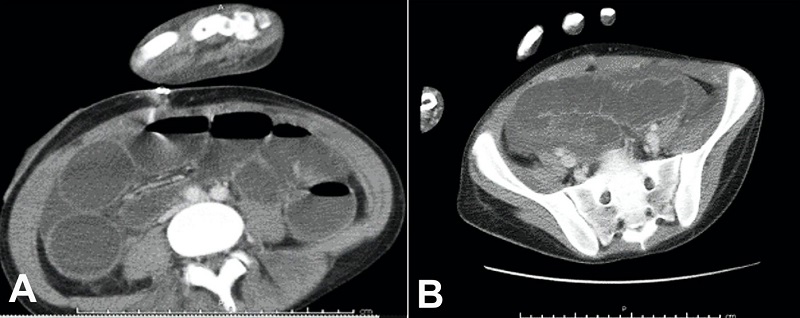

On admission, his temperature, respiratory rate, and pulse were elevated to 39.6oC, 34/min, and 126/min, respectively. His white blood cell count was 19.65 cells/μL (neutrophil predominance of 90%). The abdomen was mildly distended but nontender. Stool analysis revealed no ova, cyst, or parasite. Stool lactoferrin test for neutrophils was positive. CT scan of the abdomen showed marked thickening in the wall of the ascending colon (Figure 1).